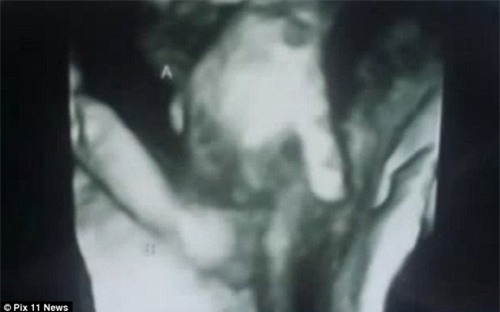

Cặp vợ chồng người Anh là Ian và Brittani McIntire không may khi một trong hai đứa con song sinh của mình bị chết khi chưa được sinh ra. Họ còn cảm thấy đau lòng hơn khi nhìn thấy hình hài bé nhỏ dù đã chết nhưng bàn tay vẫn nắm chặt lấy tay của người chị em song sinh còn lại.

Sự việc đau lòng xảy ra với thai nhi song sinh của cặp đôi người Anh Ian và Brittani McIntire. Theo kết quả siêu âm thai, các bác sĩ kết luận bé trai (được bố mẹ đặt tên là Mason) gặp bất thường ở tim và não. Cân nặng của bé cũng chỉ bằng 1/3 so với người chị song thai của mình. Điều này đồng nghĩa với việc bé đã không thể tiếp tục phát triển trong tử cung mẹ.

Thông tin này khiến cặp đôi vô cùng đau xót. Tuy nhiên, một hình ảnh khiến họ bất ngờ đó là dù thai nhi đã qua đời trong bụng mẹ nhưng bàn tay vẫn nắm chặt lấy tay của người chị song sinh.

Cặp đôi cũng đã lưu lại những hình ảnh siêu âm đặc biệt này như một kỷ vật để tưởng nhớ về bé Mason đã không may mắn qua đời trong bụng mẹ.